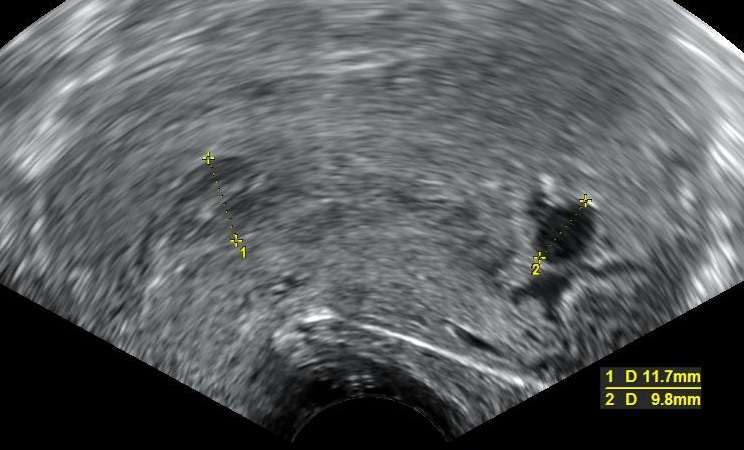

Диагнозата е редовно, за да се постави чрез изследване на нивата на хорионгонадотропин и да се вземе предвид ехографската находка от избрания преглед. Изходът зависи от много фактори, но основно налага спешна хирургична намеса, както сме обсъдили в предишната ни статия ” Хирургично лечение при спонтанен аборт ”

е подтип на извънматочната бременност. Това е, когато оплодената яйцетка се заклещи в яйчниковата тръбовата поклетка по пътя си към матката. Тубарната извънматочно бременност е много често срещана и може да се прояви както едностранно, така и двустранно.

При едностранна патология на яйцеклетката може да се локализира на погрешното място- в ампулата или в истмуса на фалопиевата тръба. Въпреки това, там всички пак съществуват добри условия за развитие до 24-та гестационна седмица. При внедряването му във фалопиевата тръба, обаче, хорионната обвивка прониква не само в съдовете на лигавицата, но и на мускулния слой или дори до серозата, което води до реалната невъзможност на яйцеклетката да се развие по-нататък.